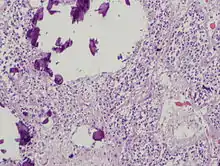

The pineal body consists in humans of a lobular parenchyma of pinealocytes surrounded by connective tissue spaces. The gland's surface is covered by a pial capsule.

The pineal gland consists mainly of pinealocytes, but four other cell types have been identified. As it is quite cellular (in relation to the cortex and white matter), it may be mistaken for a neoplasm.[16]

| Pinealocytes | The pinealocytes consist of a cell body with 4–6 processes emerging. They produce and secrete melatonin. The pinealocytes can be stained by special silver impregnation methods. Their cytoplasm is lightly basophilic. With special stains, pinealocytes exhibit lengthy, branched cytoplasmic processes that extend to the connective septa and its blood vessels. |

| Interstitial cells | Interstitial cells are located between the pinealocytes. They have elongated nuclei and a cytoplasm that is stained darker than that of the pinealocytes. |

| Perivascular phagocyte | Many capillaries are present in the gland, and perivascular phagocytes are located close to these blood vessels. The perivascular phagocytes are antigen presenting cells. |

| Pineal neurons | In higher vertebrates neurons are usually located in the pineal gland. However, this is not the case in rodents. |

| Peptidergic neuron-like cells | In some species, neuronal-like peptidergic cells are present. These cells might have a paracrine regulatory function. |